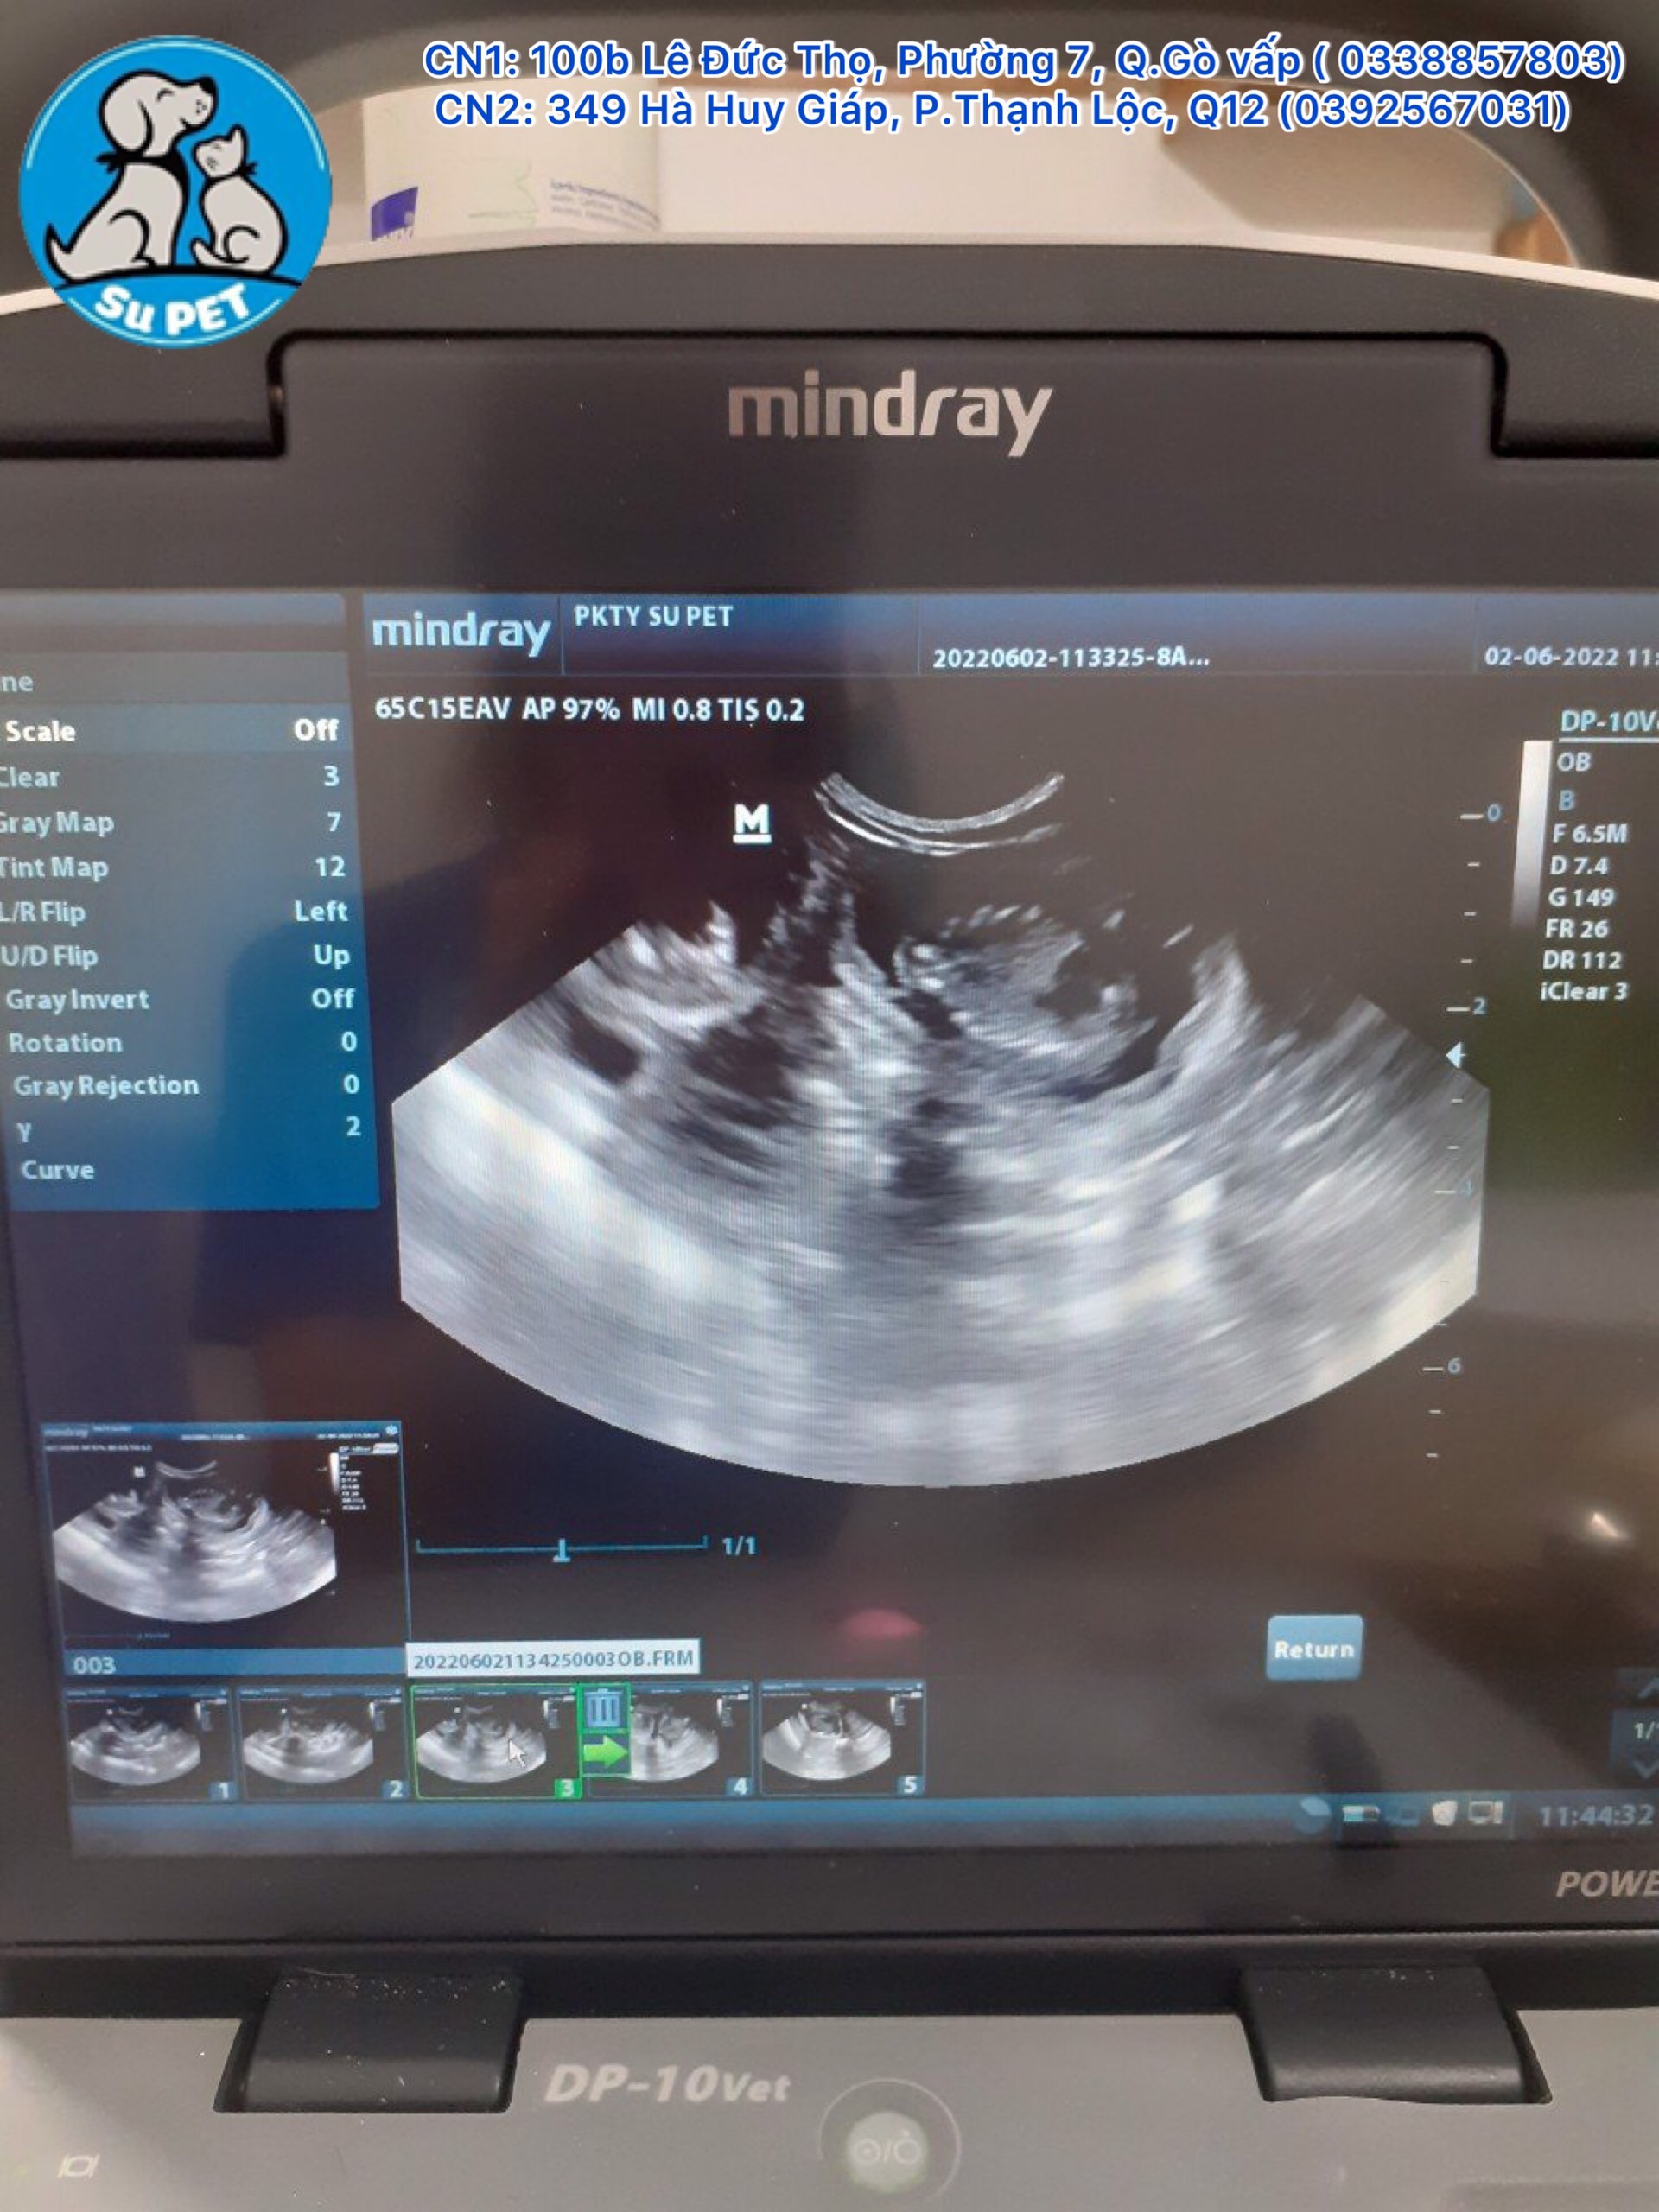

Tại Thành phố Hồ Chí Minh, có khá nhiều phòng khám thú y có dịch vụ siêu âm chó mèo. Trong số đó, Thú Y Su Pet & Spa là một trong những phòng khám hiếm hoi được trang bị máy móc thiết bị hiện đại cho dịch vụ siêu âm chó mèo.

Đến với Thú Y Su Pet & Spa, quý khách sẽ được trải nghiệm:

- Trang thiết bị và máy móc hiện đại